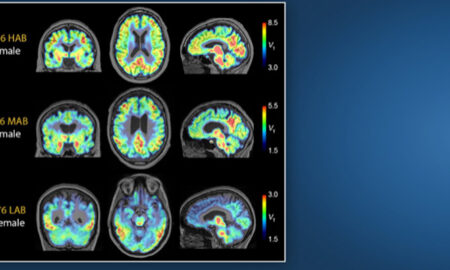

La exposición individual a la contaminación ambiental es un factor de riesgo poco reconocido y subestimado en el desarrollo de enfermedades del...